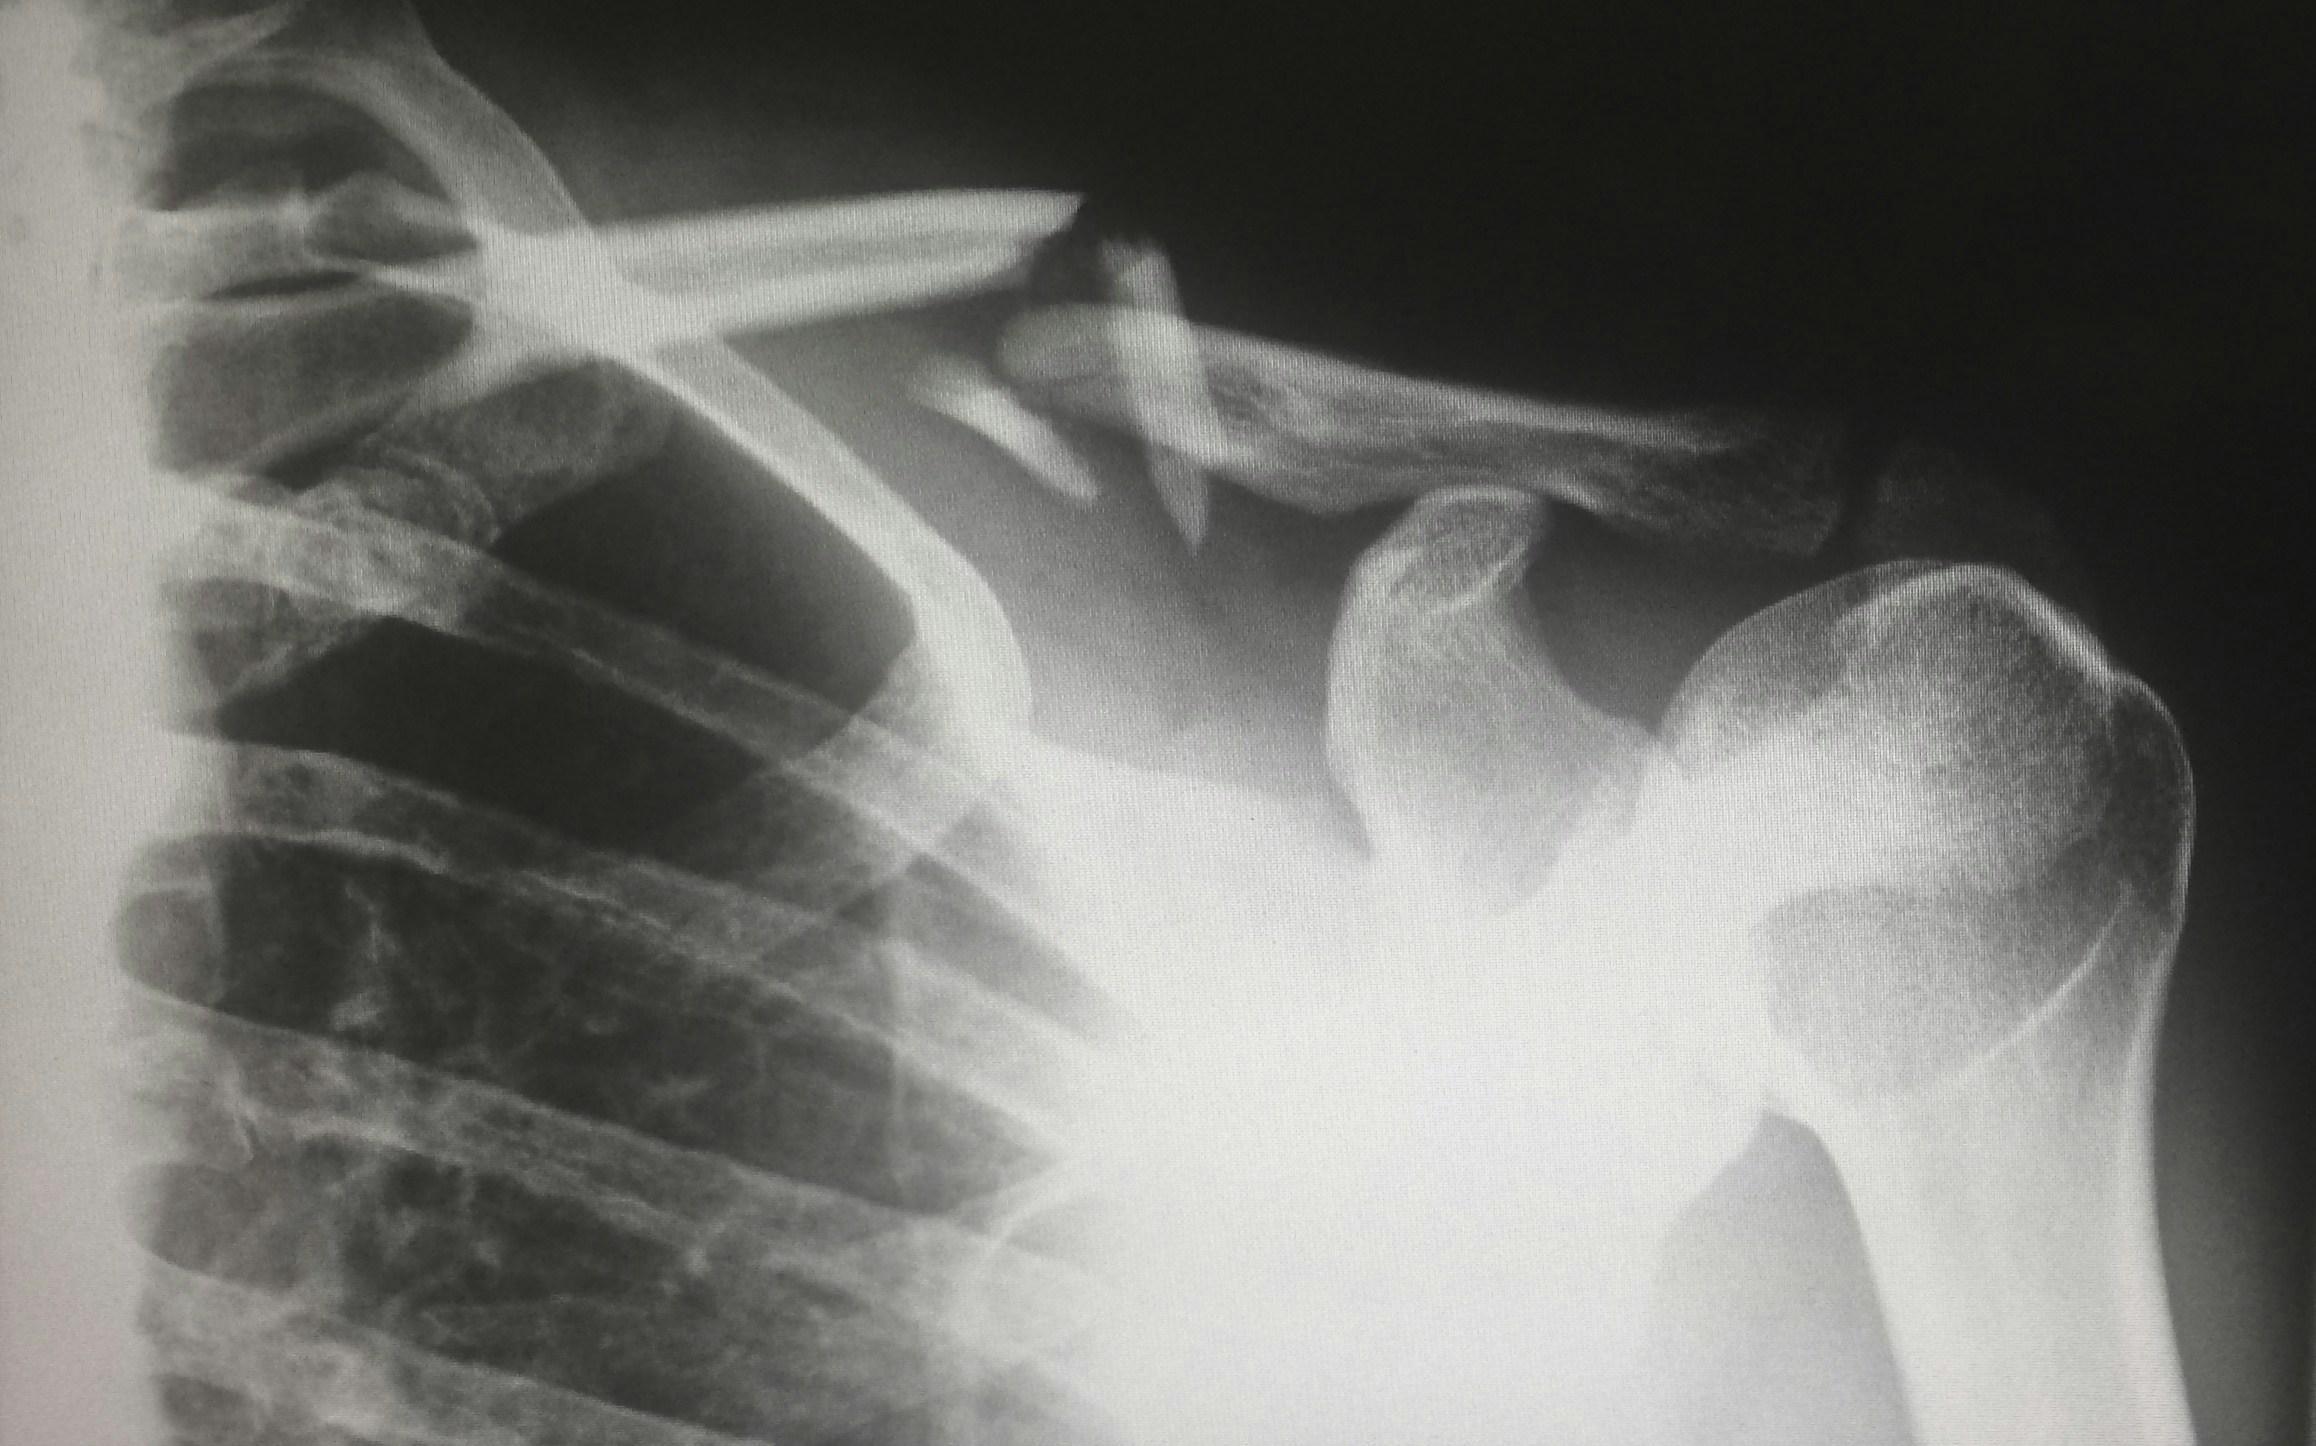

- Fracturas de hombro

Una distensión leve no se valorará igual que un desgarro completo del manguito rotador o una luxación de hombro que provoque una debilidad permanente. Las lesiones más graves suelen requerir períodos de recuperación más largos y un tratamiento más intensivo, lo que aumenta el importe de la indemnización.